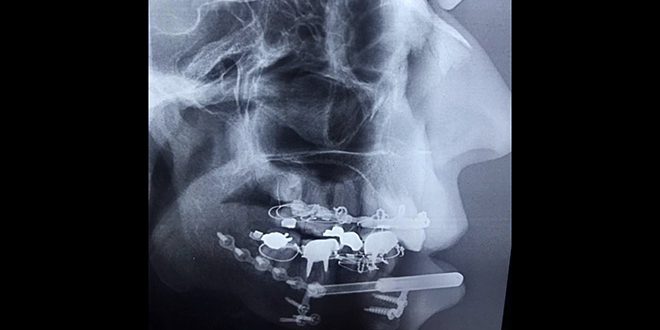

רופא השיניים המתמחה בניתוח הפנים, הפה והלסת ח’אלד עוף עלה בידו לחזיר לגברת בת 50 את הלסת התחתונה במלואה אחרי שאיבדה אותה כתוצאה לתאונה.

ד”ר עוף מסר כי בניתוח האישה סמך על מכשיר שהמציא בעבר וקיבל עליו את הפטנט, ומכשיר זה אפשר לבנות את עצם הלסת התחתונה במלואה ובלי להזדקק להסתייע בחלקים אחרים של הגוף הרחק מאזור הפגיעה כמו החזה, הרגל וכיוצא בהם.

ראוי לציין שמכשירו של ד”ר עוף מפצה את הטכנולוגיות המיושמות עתה בעולם בתחום שיקום עצמות הפנים והלסת אשר רופאים סמכו בעבר על התקנת מספר של חתיכות מתכת העולות ביוקר, אבל המכשיר של עתה תורם לחסוך את העלות העליונה וביכולתו לשרת את רוב הגילאות כולל בכך הקשישים.